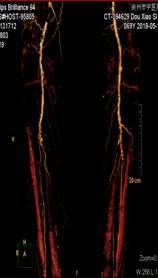

窦××,男,79岁,“右足部疼痛伴局部破溃半年”入院,间歇性跛行200米,右踝关节局部1.5×1.5cm2溃疡,第5趾底1.0×1.0 cm2溃疡,表面渗出物。糖尿病病史23年,高血压病史23年,脑梗塞病史7年。下肢动脉CTA示双下肢动脉广泛斑块形成,多发狭窄,双侧膝下动脉间断显示,大部闭塞。经药物治疗10天,疼痛消失,可自行持续行走1000米以上双下肢无不适,原足趾部溃疡愈合,踝关节部溃疡结痂。